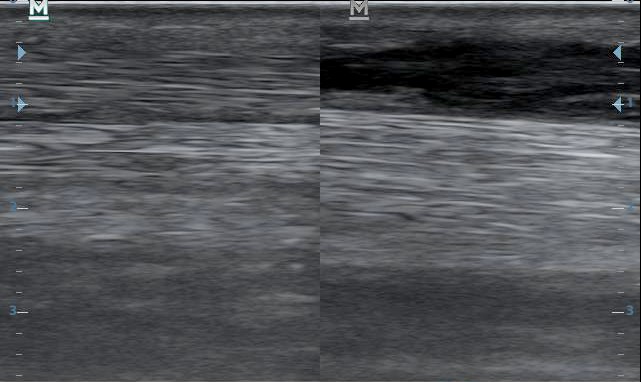

Ezt látjuk a vizsgálat során. Bal oldalon hosszmetszetben, jobb oldalon keresztmetszetben.